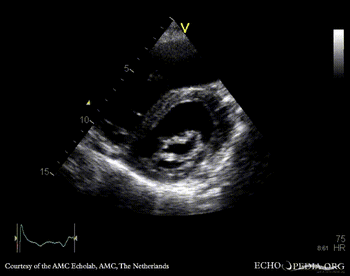

PLAX: thickend aortic valve and mitral valve PSAX: flattening of IAS, enlarged right ventricle